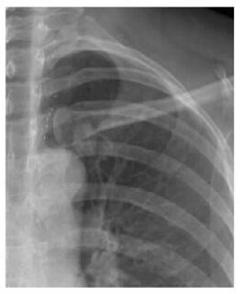

案例二:

图二 左锁骨重叠致密结节,误为衣服纽扣,病理肺腺癌

案例解析:

该病例发生在国内某基层医院,病患首先通过胸片摄影筛查,显示出左上肺野内带高密度椭圆形结节,由于形状与纽扣极为相似,误为衣服纽扣,并未做进一步诊断。第二年之后,病患再来复查,却发现照片上结节影增大,立即进一步诊断检查,最终经过活检证实为肺癌,错过了最佳的肺癌治疗期。